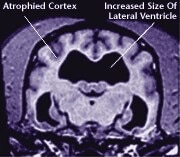

The ageing process attacks all body systems and organs in a dog, including the brain. The result is a loss of brain function, and often, the appearance of behavioural changes that were not present in a dog’s younger years.

![]() Healthy Older Brain | ![]() Older Brain with Damage |

| MRI scans show loss of brain tissue in affected dogs. Note: MRI scans are not harmful to dogs. | |